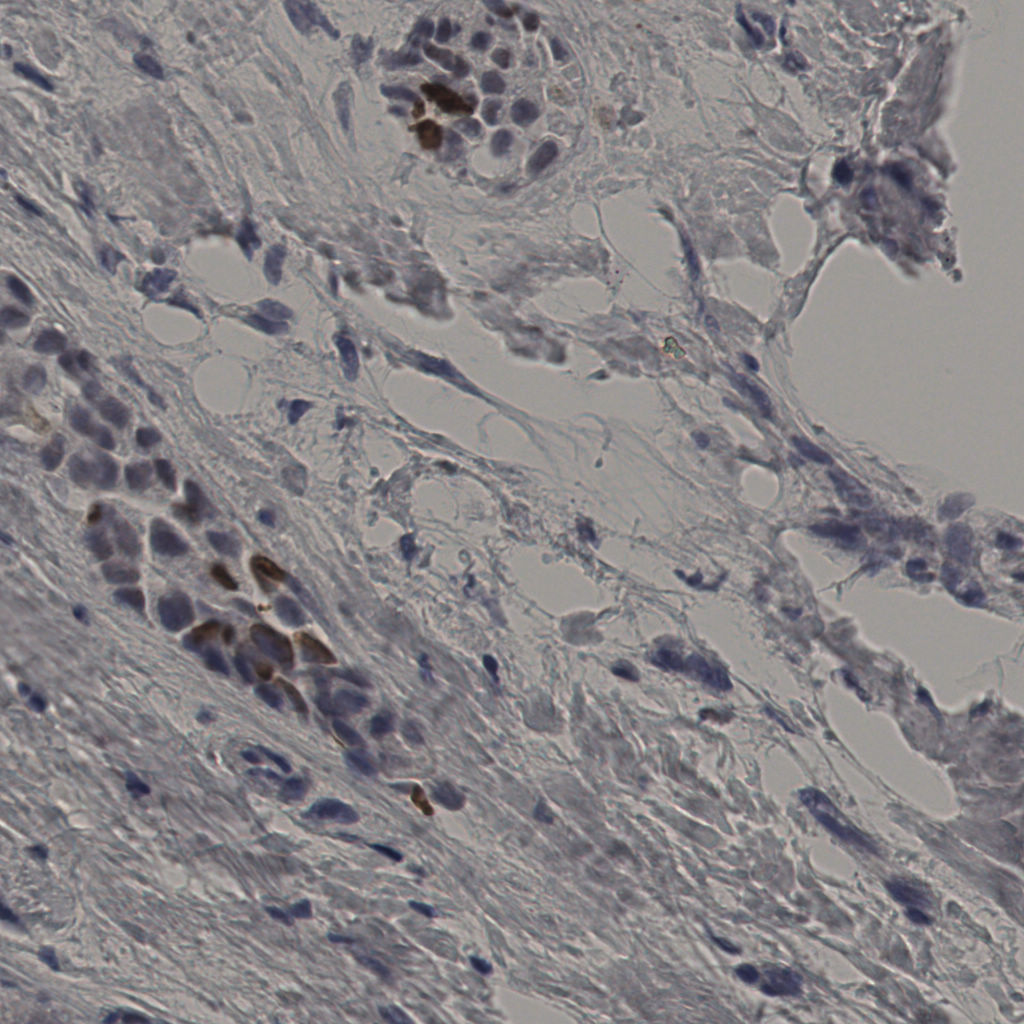

5.31%

Ki67 指数

阴 19502

阳 1093

切片统计

总切片

2970

有效

554

已标记

554

有效率

19%